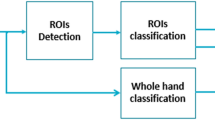

Nowadays, the integration of Artificial intelligence algorithms and quantified radiographic imaging-based diagnostic procedures is hailing amplified deliberation particularly in assessment of skeletal maturity. So we intend to formulate a logistic regression model for intelligent and quantitative estimation of Fishman skeletal maturation index (SMI) based on the parameters attained from the cervical vertebrae CBCT images of Chinese girls.

Five significant parameters (Chronological age, C3 height (H3)\()\), C4 upper width (UW4), C4 lower width (LW4), and the ratio of posterior height to lower width of C4 (\(\mathrm{PH}4/\mathrm{LW}4)\)) were administered into logistic regression model. Despite total agreement percentage which was 84% (total AUC = 0.92), unsatisfactory performance was noticed for the 6th and 8th stages which were confused with their neighboring stages. After adjustments of the models, the total agreement percentage and AUC were upgraded to 88% and 0.96, respectively.

Consistency and fitness evaluation of our models demonstrated adequate prediction percentage and reliability for automated classification of skeletal maturation. The presented constructed logistic regression model has the potential to serve as a maturity evaluation index in clinical craniofacial orthopedics in Chinese girls. The proposed model in this study showed promising strength for being expended in the event of other clinical multi-stage conditions.